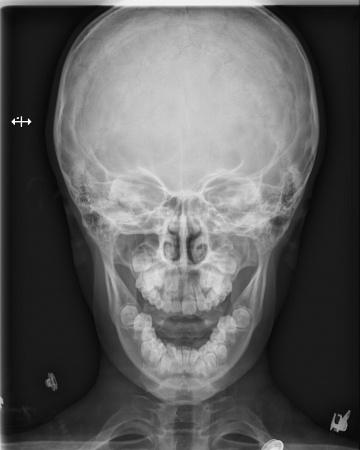

男,9岁10个月,右侧中切牙乳牙未换,右侧切牙已换。牙片显示右中切牙恒牙位置异常,与右侧切牙(恒牙)部分重叠,且右中切牙恒牙牙根稍短小(位置影响?),如何处理?能否矫正?

最好拍个**T确定恒牙位置,确定阻生的原因,再做处理!!